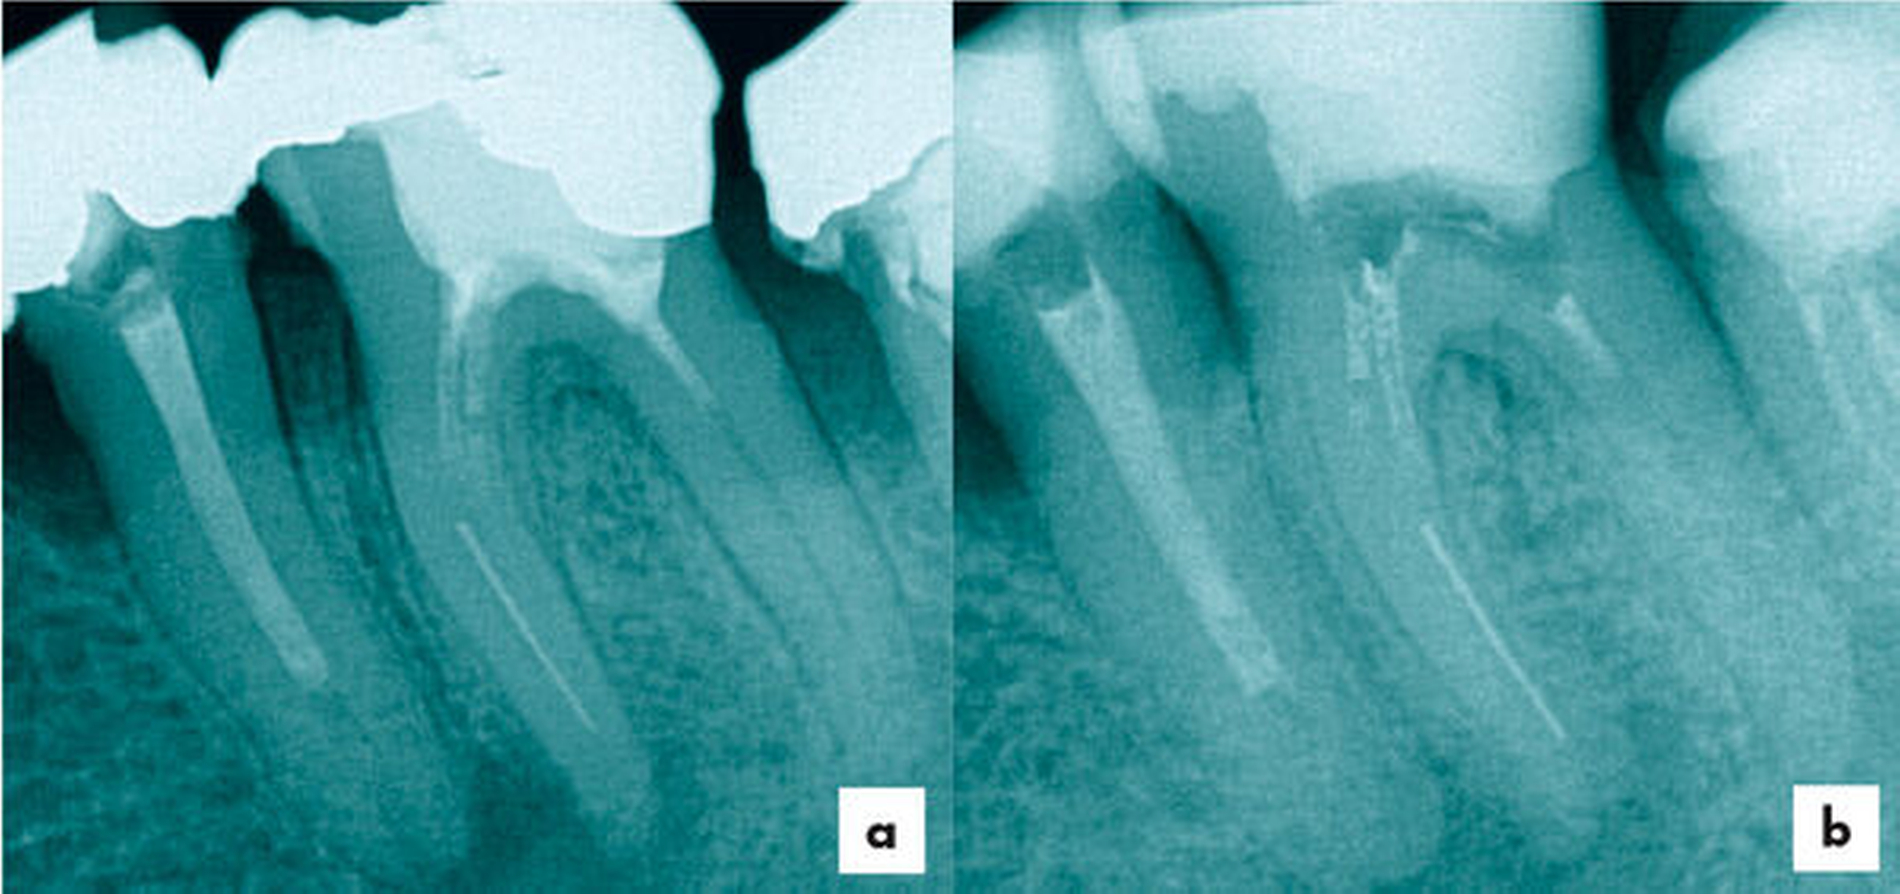

Ein 64-jähriger Patient wurde mit zwei frakturierten Hedströmfeilen in der distalen Wurzel von Zahn 46 überwiesen. Der Vorbehandler hatte versucht, das erste Fragment mit einer weiteren Hedströmfeile schraubend zu entfernen, jedoch frakturierte auch diese unter der hohen Torsionsbelastung (Abbildung 3).

Das eingeschraubte Fragment wurde koronal mittels Ultraschalltechnik (VDW Ultra, VDW, München, Deutschland; Endo-Chuck, B&L Biotech, Fairfax, USA) 3 mm freigelegt und aufgerichtet. Anschließend konnte das Fragment mit der Tube-Dorn-Apparatur gegriffen und entfernt werden (Abbildung 4). Daraufhin wurde Durchgängigkeit in allen drei Wurzelkanälen erreicht und es erfolgte die chemomechanische Aufbereitung. In der nächsten Sitzung wurde die Obturation mit Guttapercha und AH Plus (Dentsply Sirona, York, USA) warm-vertikal modifiziert nach Schilder durchgeführt (Abbildung 5).